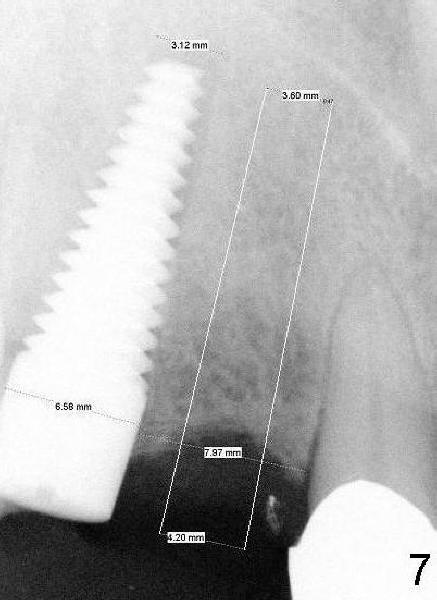

There is approximately 8 mm between the tooth #8 and the implant at the site of #6 (Fig.6,7). The distance appears to be enough to place D2 and D1 implants (Fig.6,7, respectively).

According to pre-op CBCT analysis, D1 short implant can be safely placed at the site of #7 (Fig.8,9, as compared to Fig.3). Which of D implants is the most appropriate?